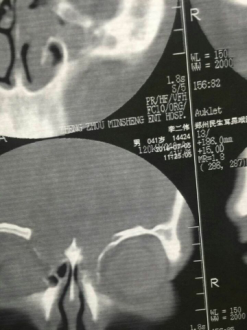

李先生来到郑州民生耳鼻喉医院接受了一系列检查后,被确诊为颅底脑脊液鼻漏,缺损比较大,情况比较严重。

7月15日手术如期举行,手术采用额外鼻内的形势进行,用李先生自身肌肉筋膜组织实现了对缺损位置的铺盖修复。

由于事前所做检查已经几乎确定了缺损位置,加上郑大一附院医生娄卫华教授的技术支持,手术中很快就在鼻内镜的帮助下,找到了缺损位置,并以快的速度做了的修复。手术进行得顺利而成功。